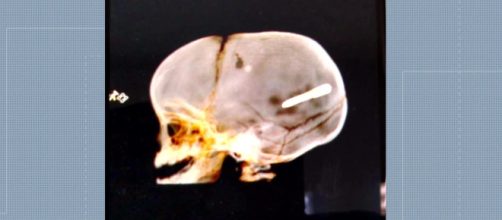

Os pais do menino relataram ainda que o objeto que atingiu a cabeça do bebê se parecia com um dardo, usado para colocar gesso em construções. Perto de onde eles estavam havia uma obra, onde, segundo os pais, estava ocorrendo uma instalação de gesso. A polícia foi até o local, mas não encontrou nenhum responsável. Uma radiografia mostrou o objeto alojado no crânio da criança.

Por conta da região do cérebro que foi atingida, os médicos não conseguiram retirar o objetivo e saber exatamente o que era. A criança chegou a passar por uma cirurgia durante a madrugada.